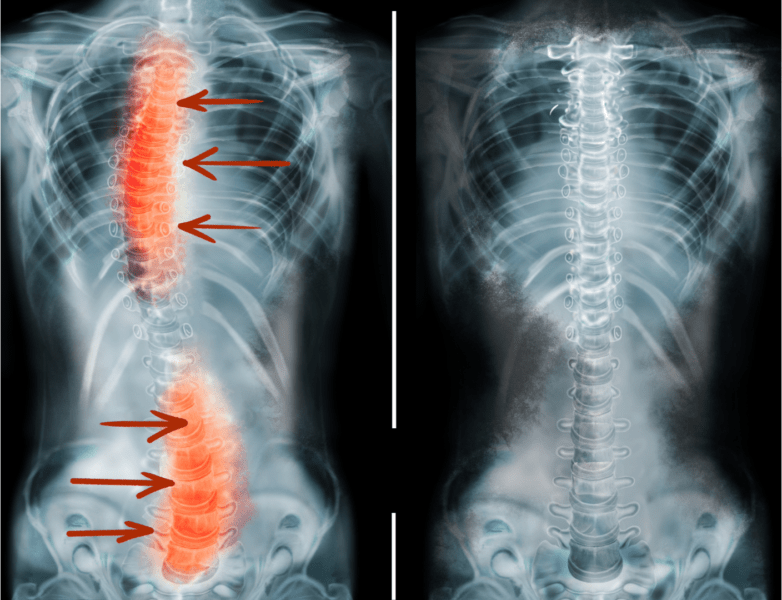

A escoliose é uma condição caracterizada pelo desvio lateral da coluna vertebral, criando uma curvatura anormal que pode assumir formato de “S” ou “C” quando vista de costas. Diferente de uma postura inadequada temporária, a escoliose representa uma alteração estrutural permanente da coluna que pode progredir ao longo do tempo se não for adequadamente tratada.

Coluna com escoliose x Coluna sem escoliose

Para entender melhor, imagine que sua coluna vertebral deveria ser como uma torre perfeitamente alinhada, vista de frente ou de costas. Na escoliose, essa “torre” apresenta curvaturas laterais que não deveriam existir, criando um desalinhamento que afeta todo o sistema musculoesquelético.